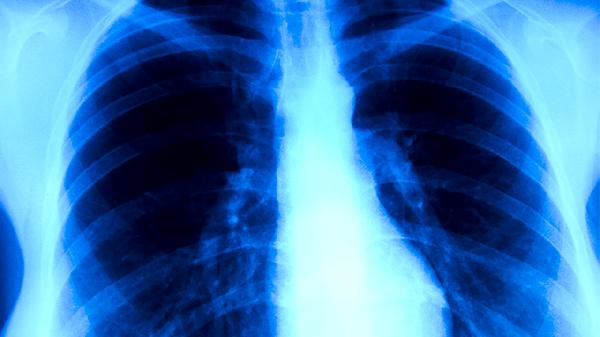

痰涂片抗酸染色鏡檢是基礎(chǔ)篩查手段,痰培養(yǎng)可提高檢出率但需2-8周。胸部X線可見上肺野浸潤、空洞或纖維化病變。γ-干擾素釋放試驗(yàn)有助于鑒別潛伏感染。分子生物學(xué)檢測如GeneXpert可快速診斷并對利福平耐藥性進(jìn)行篩查。